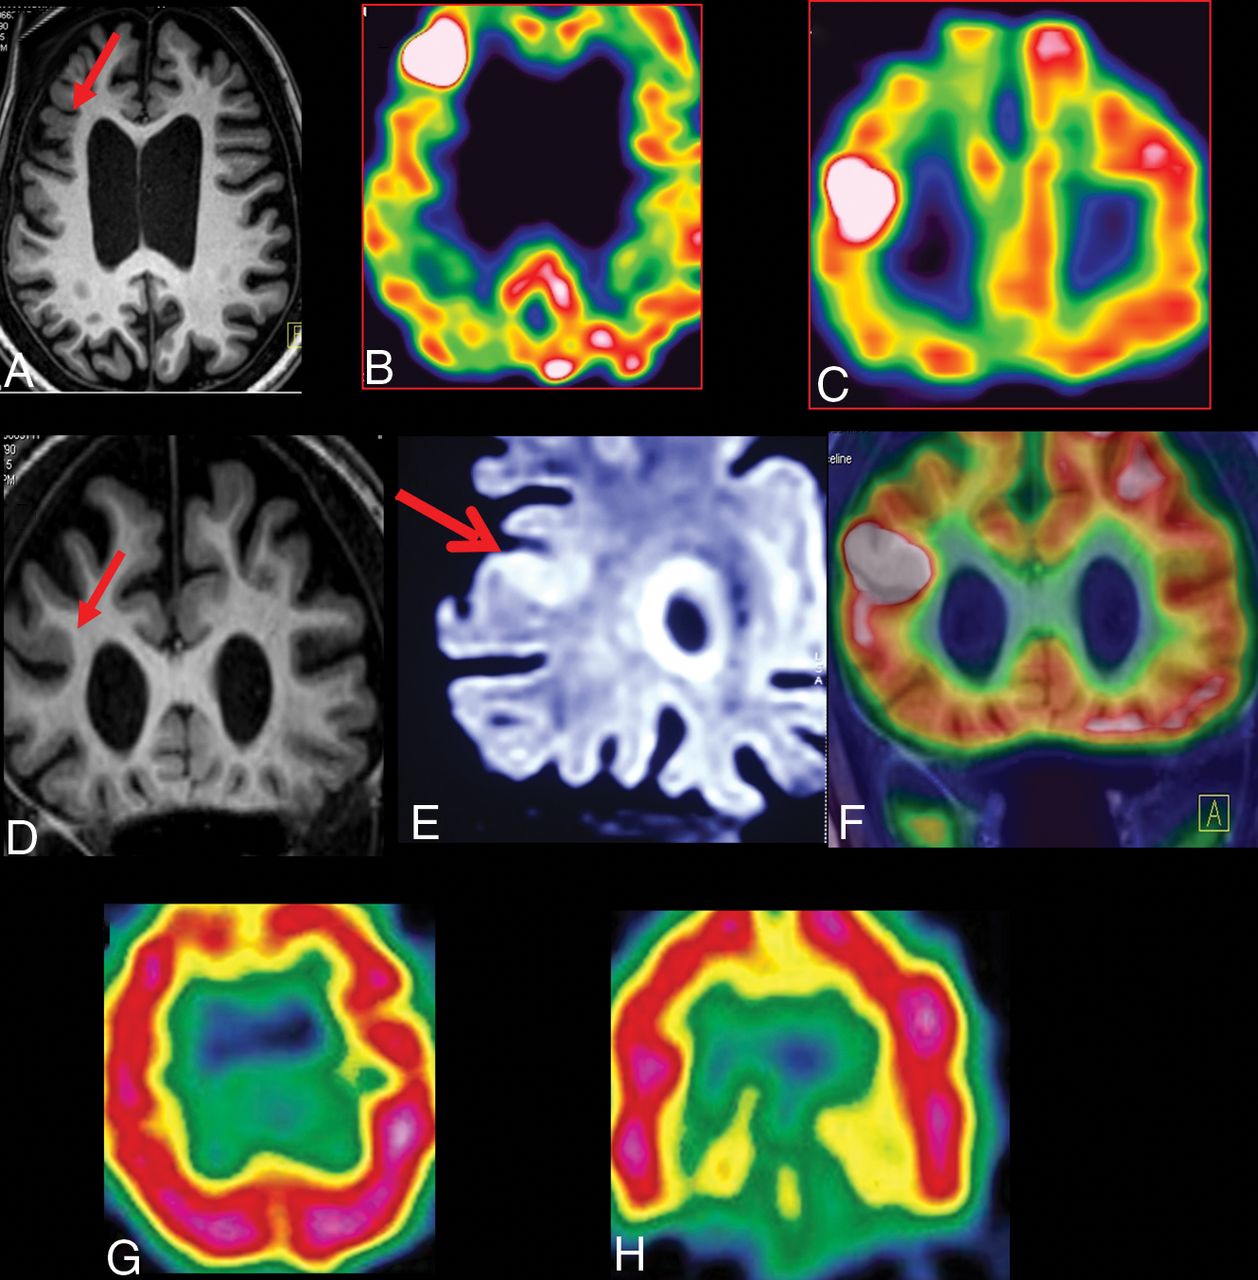

A case of refractory epilepsy with daily seizures of 21 years' duration with moderate mental retardation. Brain MR imaging 3D-T1 volume fast-field echo sequences of axial (A), coronal (D), and coronal (E) 3D-FLAIR volume show a right middle frontal gyrus cortical laminar architectural abnormality with cortical thickening (arrow). The MR imaging abnormality was detected retrospectively after the FDG-PET (B and C) and MR imaging/FDG-PET coregistration (F) showed the focal hypermetabolic focus. The ictal SPECT (G and H) findings were inconclusive.

The interictal EEG showed regional epileptiform discharges in 93 (49.5%) patients, and 88 (46.8%) had regional ictal EEG onset. Interictal FDG-PET showed hypo- or hypermetabolism in 181 (96.3%) and a focal PET pattern in 144 (76.6%). In the110 patients in whom ictal SPECT was performed, focal hyperperfusion was noted in 77 (70.3%) patients. MR imaging showed clear-cut FCD in 136 (72.3%) patients. In the remaining 52 (27.7%) patients with subtle MR imaging findings, a regional interictal or ictal EEG onset pattern was noted in 27 patients. Among these 27 patients, a focal FDG-PET pattern was observed in 21 patients (Fig 1). In the remaining 6 patients, ictal SPECT showed focal hyperperfusion in 3. Among the 25 patients with subtle MR imaging findings and in whom ictal or interictal EEG was nonlocalizing, a focal FDG-PET pattern was observed in 16 patients. Among the remaining 9 patients, ictal SPECT showed focal hyperperfusion in 3 patients. Surgery was performed in the remaining 6 patients with subtle MR imaging findings after invasive EEG evaluation.